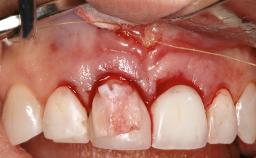

Resective Surgical Treatment of Peri-Implantitis Including Implantoplasty

In this case, Myroslav Solonko, Ignacio Sanz Sánchez and Mariano Sanz present a treatment that aims to eliminate exposed implant threads by modifying the implant surface, converting a moderately-rough surface into a smooth surface.

A 63-year-old male patient was referred to the post-graduate periodontal clinic of the Complutense University of Madrid for the treatment of peri-implantitis. According to the patient’s record, all his maxillary teeth had been extracted ten years previously due to severe periodontitis, and a full-mouth implant-supported restoration on eight implants was placed. No supportive periodontal therapy was provided apart from occasional check-ups by the restorative dentist.